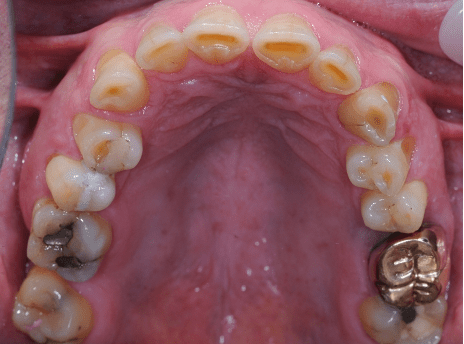

Crowns may be used to treat toothwear or broken down teeth. They are often selected where composite has failed, the teeth are too broken down or there is a need to provide a stronger material. This case was managed with surgical crown lengthening and multiple crowns. The lower incisors were treated with composite.